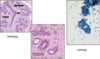

pictures showing spreading and staining

a blob of material si spread onto two slides, one into alcohol and one to dry and then stained

staining overall takes baout 5 minutes

what are the cytological features we are looking for on a microscope to decide if we are delaing with a benign or malignant tissue?

epithelial cells of glandular tissue we are intrested in as this is where breast carcinoma arises

what are aspirates of benign breasts like?

- low/ moderate cellularity

- cohesive groups of cells

- flat sheets of cells

- Bare oval (bipolar) nuclei in background

- cells of uniform size

- uniform chromatin pattern

what does malignant aspiarates look like?

- high cellularity

- crowding/overlapping of cells

- loss of cohesion (resulting is dissociated isngle cells)

- nuclear pleomorphism (larger nuclei and varrying shape)

- hyperchromasia (nuclei look dark - A morphologic finding referring to the presence of darkly stained nuclei due to abundance of DNA on hematoxylin-eosin stained sections. It is suggestive of malignancy.)

- absence of bipolar nuclei